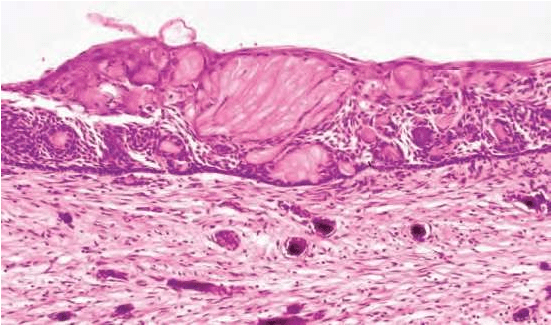

• HISTOLOGICAL FEATURES:-

1. Lining is usually thin about 6 – 8 cell thick, may be thickened in other areas.

2. Lining shows characteristic odontogenic features with reversely polarized basal cell layer.

3. TYPICALLY – GHOST CELLS may be seen in thicker areas of lining.

4. Ghost cells are enlarged, ballooned, ovoid, eosinophilic cells with well

defined cell boundaries.

5.Some times many cells may fuse.

6.They represent abnormal keratinization and frequently calcify.

7.Tubular dentinoid and even complex odontome may be found in connective tissue wall close to epithelial lining.

Histological features of a calcifying odontogenic cyst with clusters  of fusiform ghost cells and focal calcifications, lying in a stratified  squamous epithelium.

In this calcifying odontogenic cyst, there are sheets of ghost cells  and a focal area in which there has been induction of a strip of  dysplastic dentine (dentinoid).